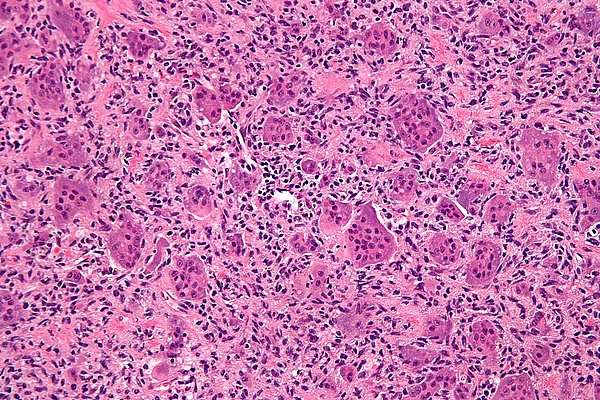

Микроскопическая структура гигантоклеточной опухоли кости, в основном, представлена двумя типами клеток. Преобладающее большинство клеточных элементов составляют веретенообразные, овальные и округлые клетки с умеренно выраженной цитоплазмой и светлым ядром, содержащим небольшое количество хроматина. В ядрах определяются одно, а иногда два хорошо различимых ядрышка, могут выявляться фигуры митоза, как правило, типичные.

Другим клеточным компонентом являются многоядерные гигантские клетки. Эти клетки очень похожи на нормальные остеокласты, но обычно несколько крупнее их и имеют закругленный контур. Они содержат 20-30 и более ядер, большинство из которых располагаются в центре клетки. Ядра многоядерных клеток обычно лежат изолировано друг от друга и, практически, не отличаются от ядер одноядерных клеточных элементов. Цитоплазма этих клеток слегка базофильна. В многоядерных гигантских клетках фигур митоза не определяется. Эти клетки равномерно (важный дифференциальный диагностический признак!) расположены в опухоли.

Многоядерные гигантские клетки остеокластом имеют множество общих характеристик с типичными остеокластами. Кроме морфологического сходства они обладают общими ультраструктурными чертами (зазубренный край и обилие митохондрий), гистохимическими свойствами (высокая активность кислой фосфатазы и других гидролитических энзимов) и иммуногистохимическими проявлениями (экспрессия лизоцима, α-1-антитрипсина, α-1-антихимотрипсина и других маркеров). Кроме того эти клетки содержат рецепторы кальцитонина – фенотипического маркера остеокластов.

Природа одноядерных клеток опухоли иная и их ультраструктурные черты подобны таковым фибробластов и остеобластов. Тесные гистогенетические взаимоотношения одноядерных клеток и остеобластов подтверждаются тем, что среди одноядерных иногда выявляются очаги костеобразования. Скопления остеоида и молодых костных балочек удается обнаружить в 30% наблюдений. Одноядерные клетки гигантоклеточной опухоли продуцируют коллаген 1-го и 2-го типов и имеют рецепторы паратиреоидных гормонов. Они не экспрессируют макрофагальный поверхностный антиген, но могут содержать лизоцим и α-1-антитрипсин. В одноядерных клетках может быть высокая активность белка S-100.